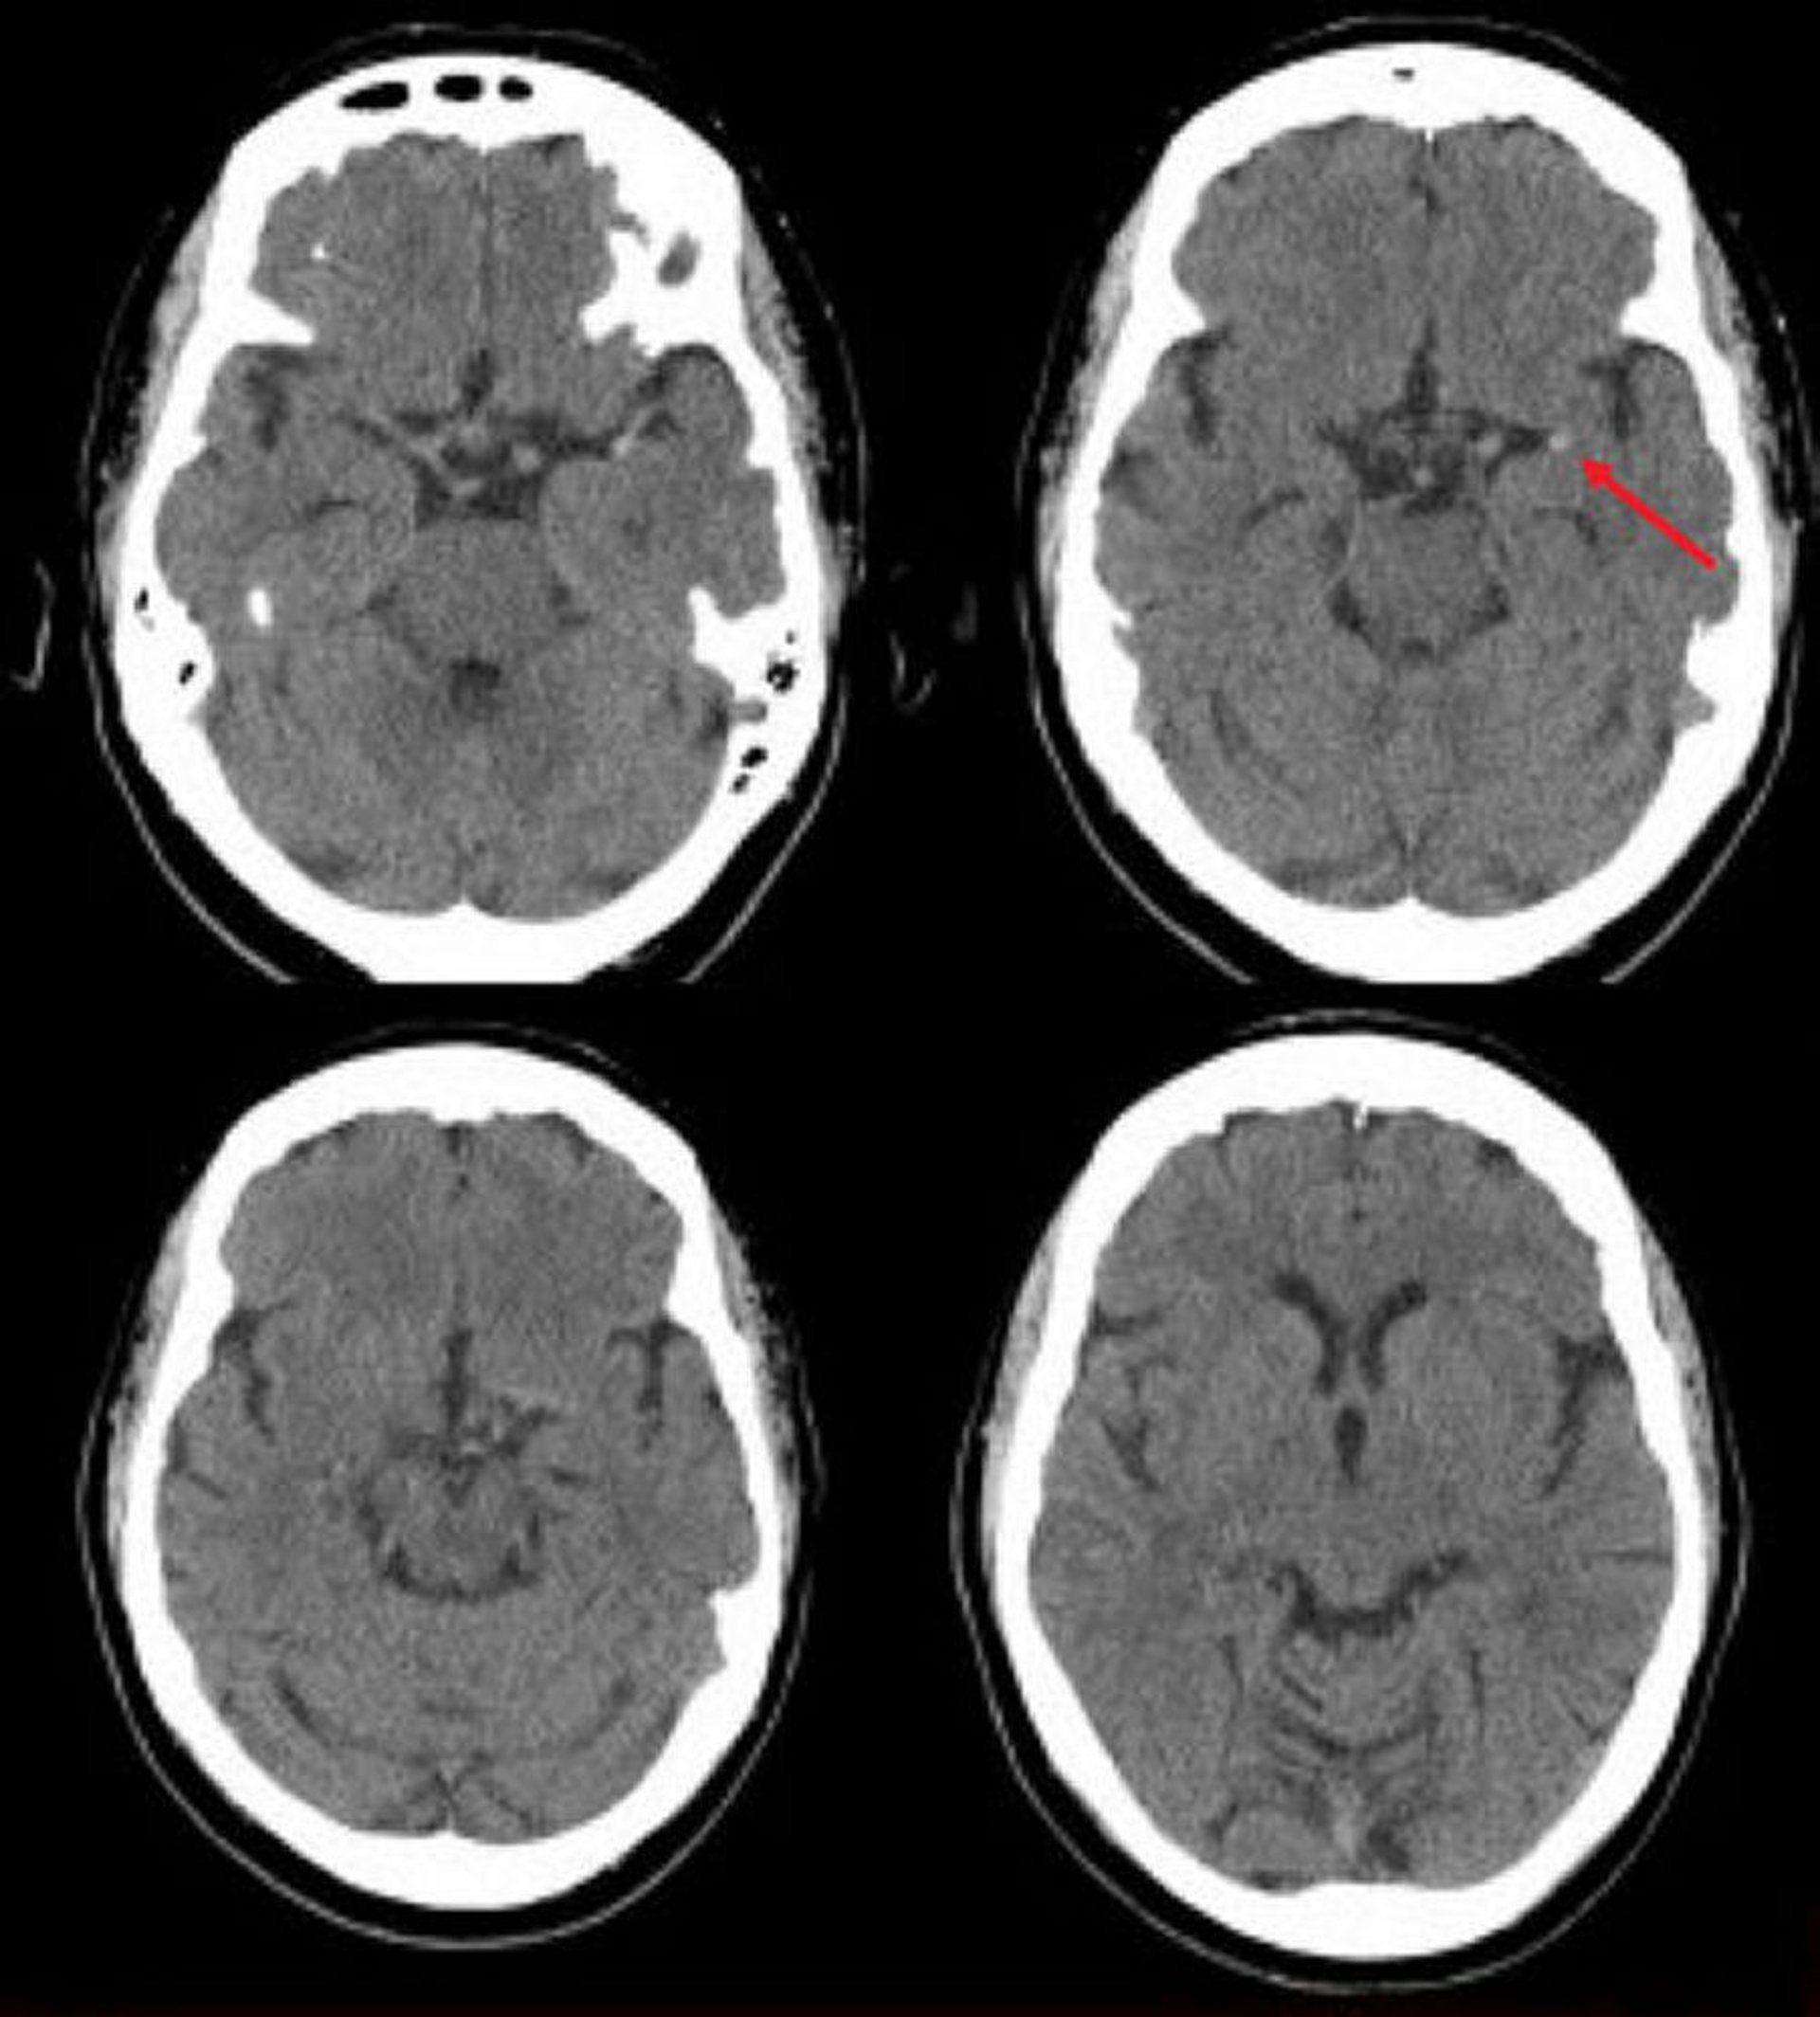

左中大脳動脈の虚血性脳卒中(CT)

この頭部単純CTでは,左中大脳動脈に高吸収域が認められる。この所見は左中大脳動脈の局所的な血栓(矢印)を示唆する。

Image courtesy of Ji Y.Chong, MD.